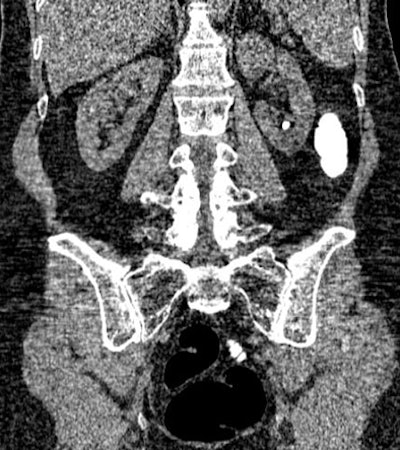

| Above, 14-mm right-sided kidney stone detected at virtual colonoscopy. Below, coronal image shows a left lower pole calculus. All images courtesy of Dr. Perry Pickhardt. |

![]() |